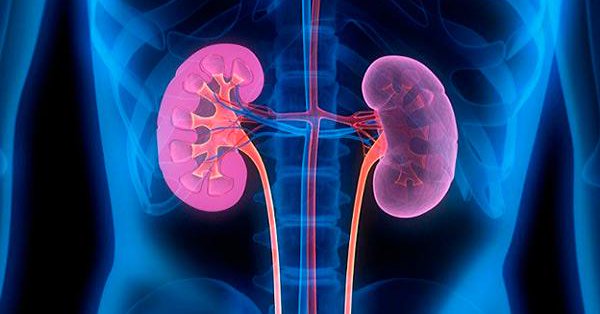

Uso de inhibidores de la bomba de protones y el riesgo de lesión renal aguda en pacientes con artritis reumatoide: estudio de cohortes

Drug Saf, agosto de 2018 Este estudio de cohorte entre pacientes con artritis reumatoide encontró un riesgo significativamente mayor de lesión renal aguda asociada con el uso de inhibidores de la bomba de protones. Estos hallazgos pueden ayudar a informar la toma de decisiones clínicas cuando se consideran los riesgos y beneficios del tratamiento con inhibidores de la bomba de protones en la artritis reumatoide.